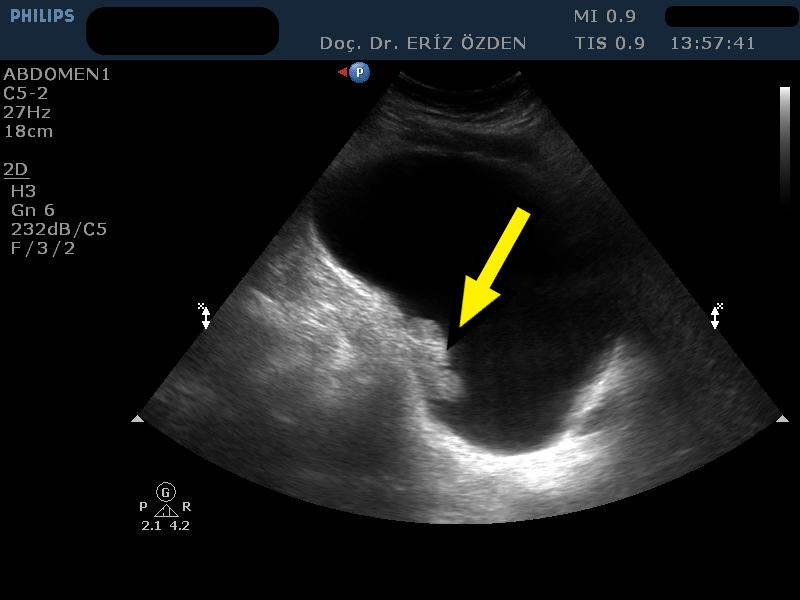

İdrarda kan görülmesi: İdrarda kan görülmesi, yapılan idrar tahlilinde kan hücrelerinin saptanması (mikrohematüri) ya da gözle görülebilir bir kan olması (makrohematüri) olarak ikiye ayrılabilir. Kan sulandırıcı kullanan hastalarda, idrar yolu enfeksiyonlarında, prostat büyümelerinde, böbrek ve idrar yolundaki taşlarda veya mesane tümörlerinde idrarda kan görülebilir. Bunlar hakkındaki ayırıcı tanı için Üroloji doktorunuz sizi muayene edecek ve idrar tahlilinizi ayrıntılı olarak değerlendirecektir. Eğer kanama mesane tümörü şüphesi uyandırıyorsa, ilk yapılacak görüntüleme tetkiki ultrasondur. Özellikle gözle görülecek miktarda, tekrarlayan, ağrısız ve/veya pıhtılı kanamalar mesane tümörü şüphesi yaratmaktadır. Ultrason incelemesi ile mesane içindeki taş, pıhtı veya tümörler görülür. Ultrason canlı görüntü veren bir yöntem olduğunda, hasta yan çevrilerek mesane içindeki oluşumun hareket edip etmediği görülür ve bu sayede mesane tümörü tanısı daha net konulur. Ultrason 5 mm’den küçük mesane tümörlerini gösteremeyebilir. Bu yüzden, Üroloji doktorunuz gerek duyarsa sistoskopi adı verilen yöntemle, idrar kanalından mesane içine girerek bir kamera yardımıyla inceleme yapar.